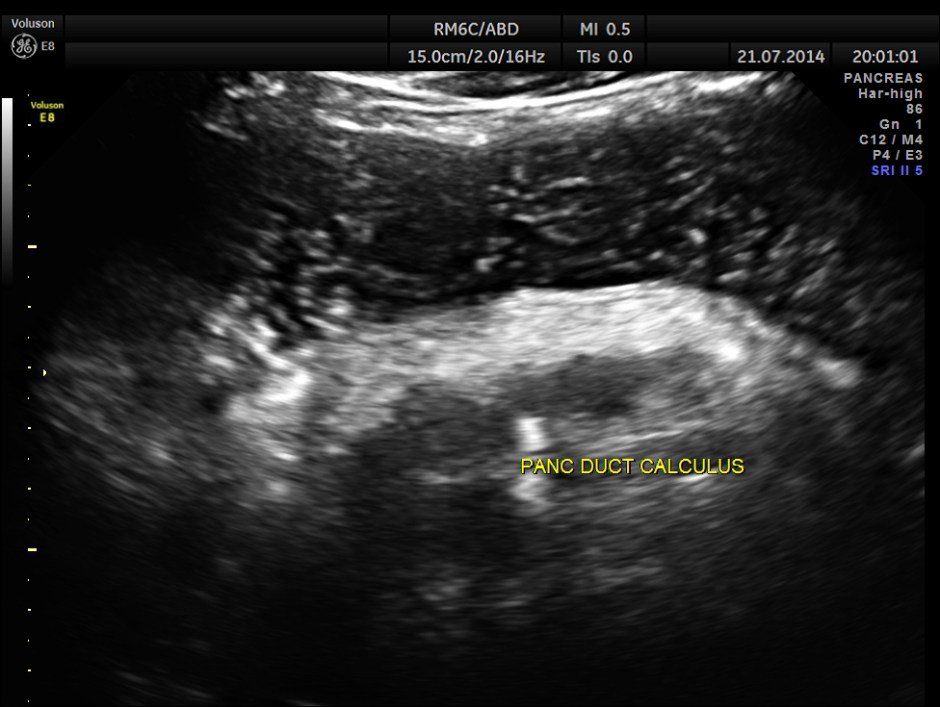

The following pictures show the pancreas.

Pancreatic calculi are seen.